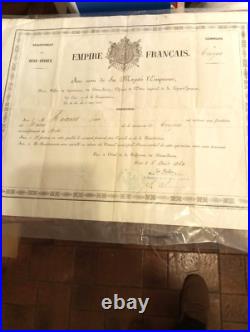

Ecole de Pharmacie de Paris (1836) : Diplôme de pharmacien 1836. La création et l’organisation de l’Ecole de Pharmacie de Paris datent de la loi du 11 avril 1803 et du décret du 8 octobre de la même année. De sa création en 1803. À son rattachement à l’Université en 1840, aucun acte législatif ou règlementaire majeur ne vient modifier la situation de l’école. En 1803 comme en 1836, date de ce document, des professeurs de l’Ecole de Médecine de Paris siègent dans les jurys d’examen. Ceci explique que ce diplôme soit délivré par les «. Professeurs à l’Ecole de Pharmacie de Paris, et Professeurs à l’école de médecine de la même Ville. Pour l’Ecole de Médecine. Médecin et chimiste espagnol, naturalisé français en 1818, il est un pionnier de la toxicologie médico-légale. Il signe ce document deux fois. La première en qualité de professeur, depuis 1819, à la faculté de médecine de Paris. La seconde comme doyen (1831 à 1848) de cette même école. Depuis 1834, il est également membre du Conseil royal de l’Instruction publique. Reçu docteur en médecine en 1820, il devint aide naturaliste au Muséum d’Histoire naturelle en 1827. En 1831, il obtient la place de professeur d’histoire naturelle médicale à la Faculté de Médecine de Paris, reprenant ainsi la fonction de son père, le botaniste Louis Claude Richard (1754 -1821). Pour l’Ecole de Pharmacie. Reçu maître en pharmacie en 1787, il s’adonne ensuite à la chimie. Attaché comme pharmacien à la maison de l’empereur, il accompagne Napoléon Ier lors de ses campagnes en Autriche et en Prusse. Lors de la fondation en 1803 de l’école de pharmacie, il occupe la chaire de chimie. En 1829, il devint directeur-adjoint et en 1832 directeur. C’est à ce poste qu’il signe ce diplôme. Pharmacien et chimiste français. Il fait d’importantes recherches sur les alcaloïdes d’origine végétale et découvre avec Joseph Caventou la quinine et la strychnine. Figure éminente de la pharmacie et de la chimie, ses recherches mettent en évidence plusieurs principes actifs comme la caféine, la narcotine et surtout la codéine. Louis René Le Canu. Il fait notamment paraître plusieurs mémoire sur le sang, sujet qui ne cesse de l’occuper pendant toute la durée de sa carrière. Document su vélin (335 x 216) avec frontispice au coq et « caducée exotique ». Diplôme délivré à Paris le 2 février 1836 et attribué à Joseph Alexandre BLANCHART. Ce dernier, né en 1812 à Péruwelz en BELGIQUE d’un père pharmacien, bénéficie d’une dispense d’âge pour ses examens. Diplôme avec un pli dans le sens de la longueur et trois dans la largeur. Les produits proposés à la vente sont de nature, de poids et de tailles très hétérogènes. Le paiement est considéré comme « soldé » une fois que l’argent envoyé par l’acheteur a été déposé sur le compte du vendeur. Paiement en ligne par carte bancaire. Par virement national ou international.